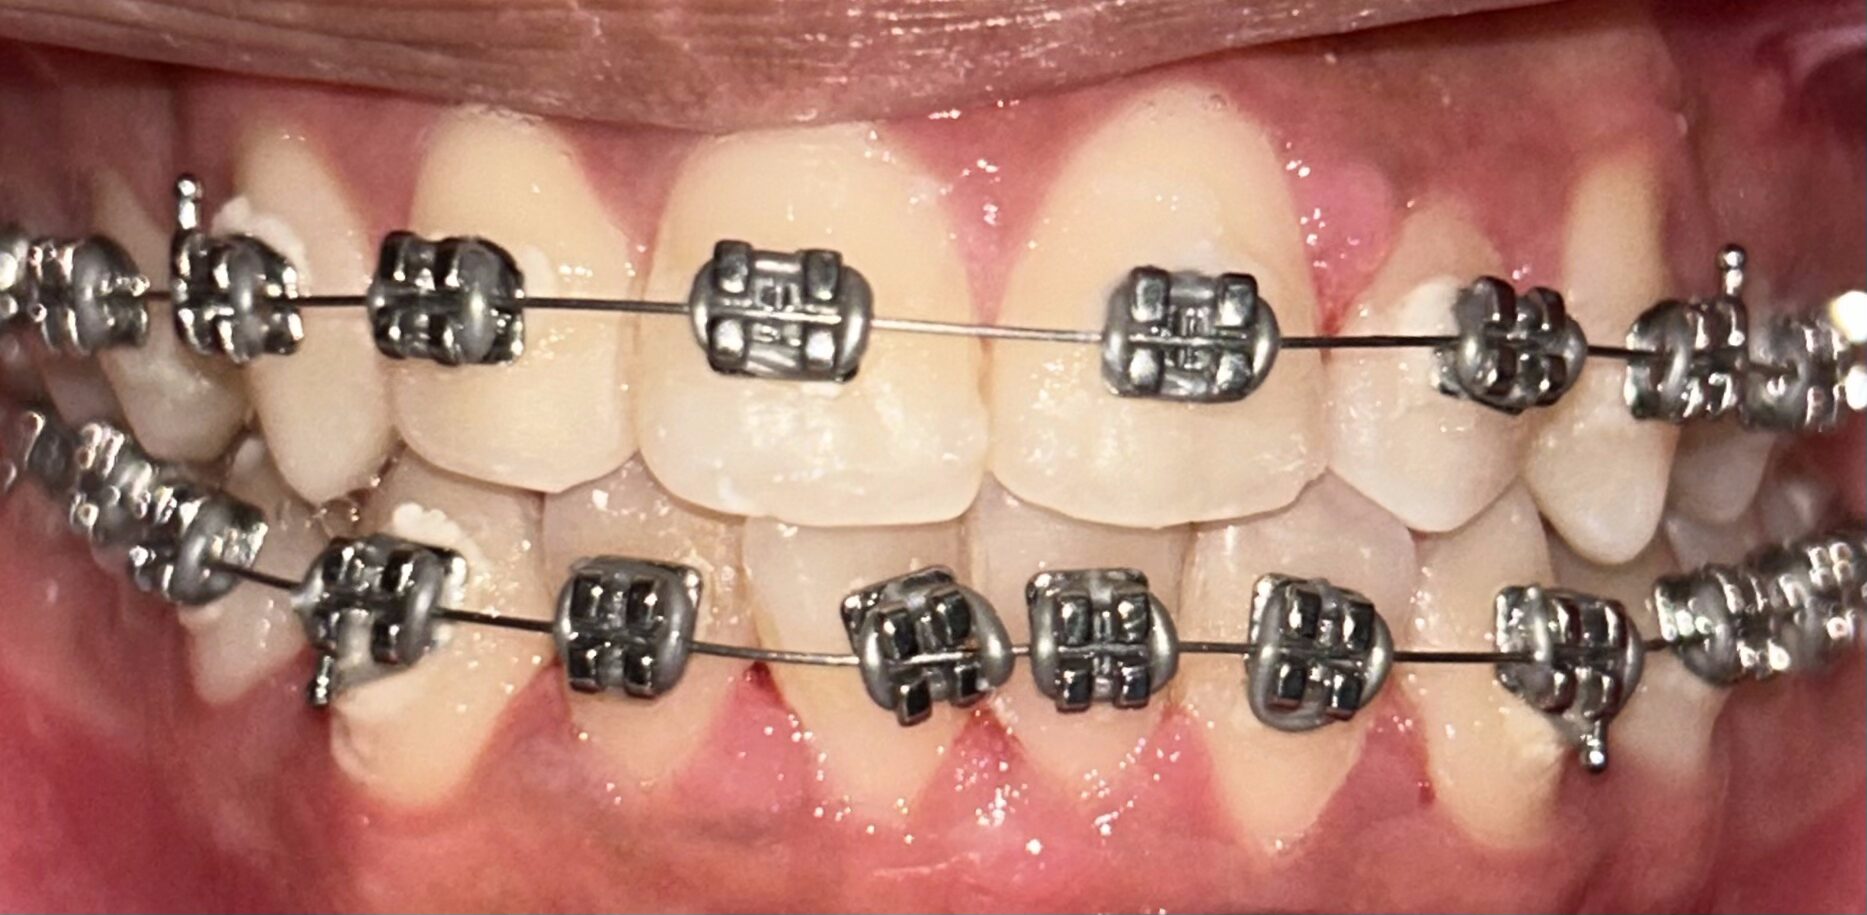

Pemasangan Behel

Merapikan posisi gigi untuk estetika dan kesehatan gigi yang lebih baik.

Pemasangan Behel

Merapikan posisi gigi untuk estetika dan kesehatan gigi yang lebih baik.